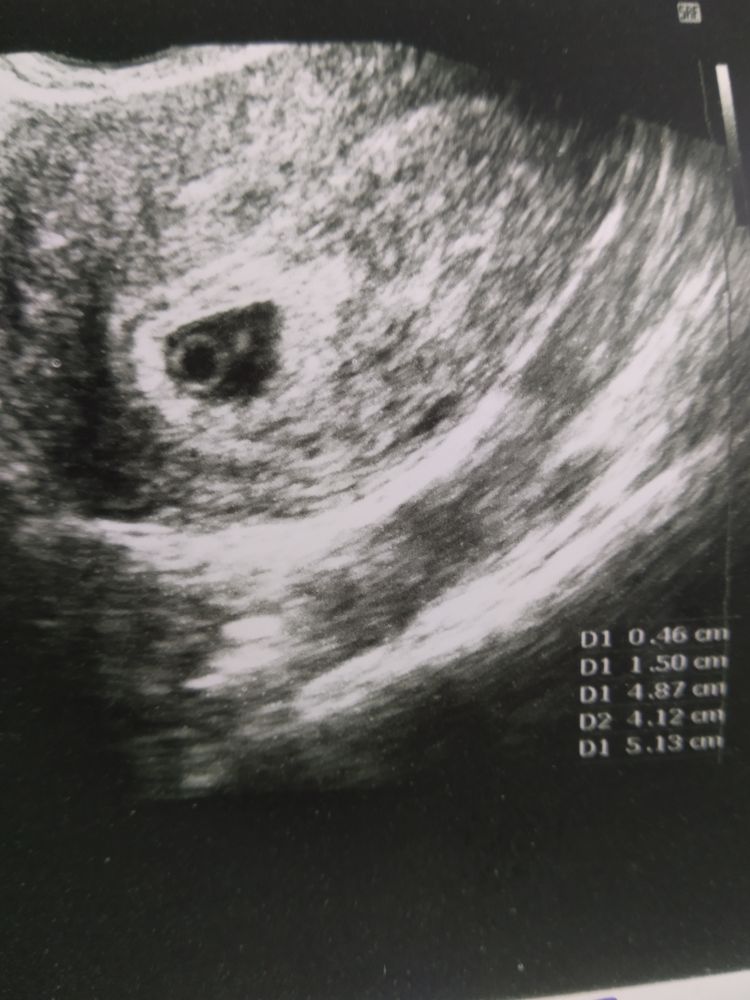

Девочки, сегодня день х Доброй ночи, дорогие)